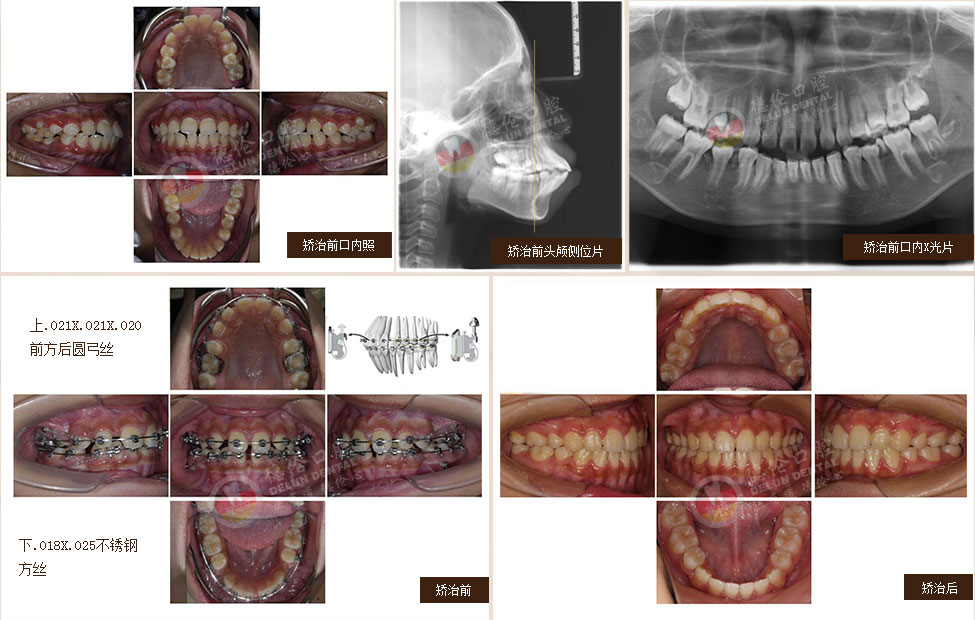

• 女:19歲

癥狀:上下前牙前突(雙牙弓前突)

矯治方法:SPEED自鎖矯治器治療 拔除上下第一雙尖牙、排齊上下牙列、內(nèi)收上下牙弓,改善面部側(cè)貌。